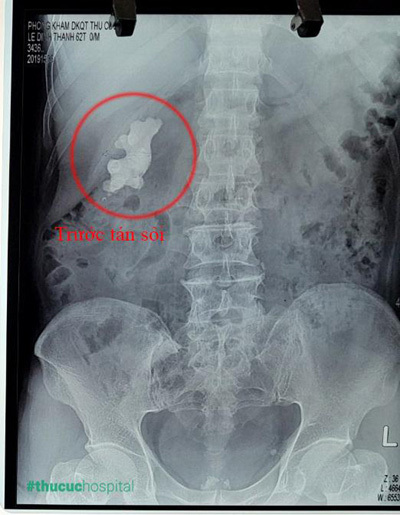

Trường hợp ông L.Đ.Thanh (62 tuổi) là 1 ví dụ điển hình. Ông Thanh đến khám tại Bệnh viện Thu Cúc trong tình trạng tảng sỏi đã phát triển quá lớn, hình ảnh trên máy siêu âm cho thấy kích thước viên sỏi của chú đã lên tới 7cm và xâm lấn gần hết thận phải. Đặc biệt, sỏi thận của ông Thanh lại là dạng sỏi san hô - 1 trong những loại sỏi cực kỳ cứng đầu và khó điều trị.

| Hình ảnh “củ gừng” - tảng sỏi san hô 7cm trong thận của bệnh nhân. |